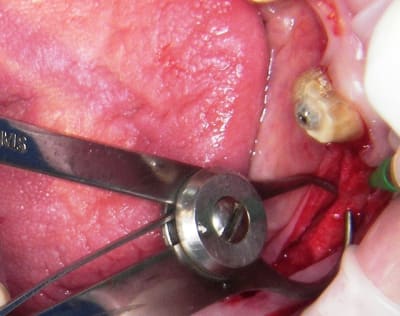

ce qui a motivé le post, c'est une journée de 12 h en continu, assistante comprise, prothésistes en relais et je me suis laissé allé à travailler sur une crete de 1mm de large, (mandibule)qui n' a pas cassée et que j'ai ammenée à 4mm, puis vitalos, mais pas d'implant (du moins pas à cet endroit)voir photos, et pour une 47 (autre cas) je me suis fais une grosse chaleur alors que tout se passait bien, en vissant l'implant la corticale linguale a rendue l'ame et j'ai tout enfoncé, implant porte implant jusqu'à la garde, chaleur!